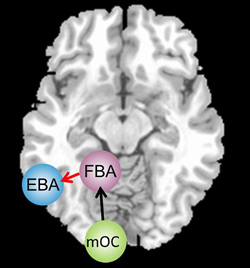

이후 연구팀은 자기공명영상(MRI) 스캐너를 이용해 이들이 몸의 실루엣 사진을 볼 때 뇌 활동이 어떻게 변하는 지 촬영했다.  시각적인 정보는 후두엽(mOC)에서 처리된 뒤 좌뇌의 FBA(방추형 영역)와 EBA(선조 외 영역)에서 분석되는데, 실험 결과 신경성 식욕 부진증을 겪는 여성이 FBA와 EBA간 연결 기능이 떨어지는 것으로 나타났다. 이같은 ‘연결 오류’는 저체중인데도 자신이 뚱뚱하다고 응답한 사람에게서 더 뚜렷하게 나타났다.